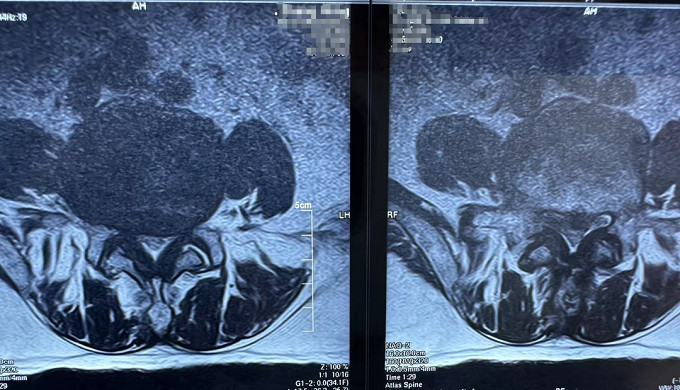

術(shù)前

核磁共振(腰椎)

可以明顯的看出,患者術(shù)前椎間盤突出壓迫到了神經(jīng)。